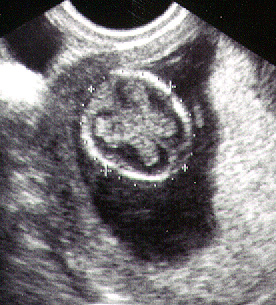

توأمان في الاسبوع الخامس

يبدأ الجنين في الأسبوع الخامس في بداية تكوينه ويسمى في هذه الفترة وحتى 3 شهور (حميل) والحميل هو الجنين منذ بداية تلقيح البويضة وحتى الأسبوع 12. فهو الآن ينمو داخل الرحم. وينقسم إلي ثلاث طبقات تكون كل طبقة منهم الأعضاء والأنسجة فيما بعد. وفي مؤخرة الرأس لأسفل، هناك طبقتين نسيج تكون الأذن بعد ذلك.